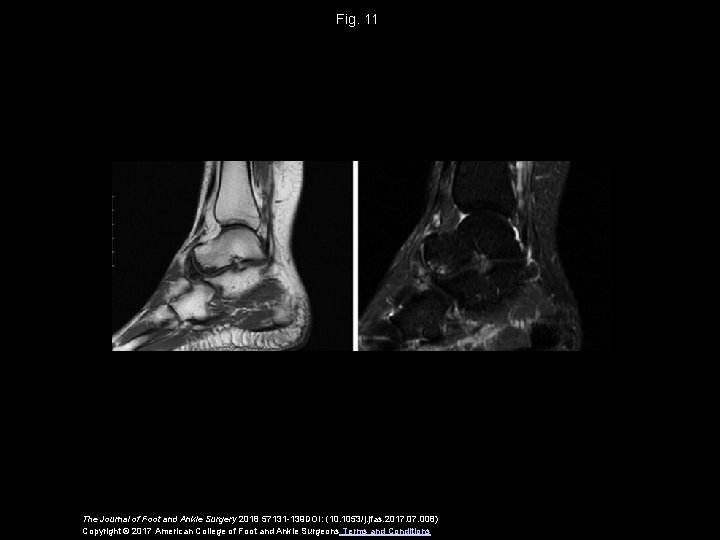

Fig. 11 The Journal of Foot and Ankle Surgery 2018 57131 -139 DOI: (10. 1053/j. jfas. 2017. 008) Copyright © 2017 American College of Foot and Ankle Surgeons Terms and Conditions